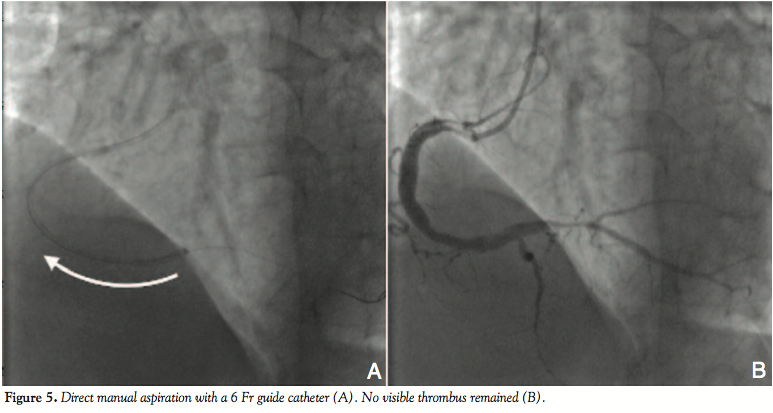

Case Report 2. A 56-year-old male was admitted to our hospital with acute central chest pain lasting 1 H. He had a history of hypertension, hypercholesterolemia, and cigarette smoking. ECG on arrival showed negative T waves in leads II, III, and aVF, and he was diagnosed with non-ST-segment elevation acute MI. He received 200 mg of aspirin orally and 5,000 units of heparin intravenously, and he underwent emergency CAG. Initial CAG demonstrated an acute large thrombus in the distal RCA with distal flow delay (Figure 4A). PCI was performed via the right transradial artery using a 6 Fr Judkins Right GC (JR-4.0, HeartRail II, Terumo Corporation). Thrombectomy was attempted several times with an

aspiration catheter (ASPREY Plus; Kawasumi Laboratories, Inc.) (Figure 4B). Scant red thrombus was collected in several aspirations, but the angiographic appearance differed little (Figure 4C). We passed the Judkins Right guide catheter into the distal RCA over the guidewire and performed manual aspiration (Figure 5A). A large, red thrombus was successfully aspirated from the culprit lesion. Subsequent injection revealed significantly improved angiographic appearance, no haziness of the distal RCA lesion, and good flow recovery (Figure 5B). Because of the vessel size discrepancy proximally and distally to the culprit lesion and no signs of residual thrombus or distal embolization, no additional intervention (such as balloon angioplasty or stenting) was performed. His subsequent clinical course was uneventful with no further elevation of cardiac enzyme levels.